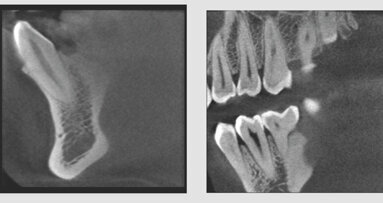

Suni Medical Imaging is the only Silicon Valley manufacturer of Digital Radiography Systems in the United States. Headquartered in San Jose, Calif., Suni manufactures and delivers high-quality digital radiography sensors under the Dr Suni Plus and SuniRay brands. The company also offers the SuniCam II intraoral camera line as well as the Suni 3D Digital Panoramic, Cephalometric, and Cone Beam 3D Systems.

Suni Medical Imaging, a company based in San Jose, CA, USA, has introduced what it calls the only 3D Cone-Beam CT (CBCT) System for the dental and ...